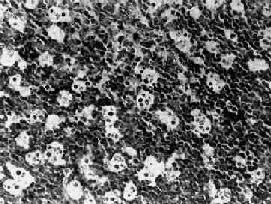

������С������������ϸ�������������������¼�������ϸ������������ϸ����С���ƣ���̬��һ�������٣����ȼ��Լ����Ե����������ԡ���������һЩ֬��С���ݡ�ϸ���˽ϴ�Բ����Բ�Σ�Ⱦɫ��ϸ������2��3�����Եĺ��ʣ��˷�������������ϸ�������ԡ���������ϸ�������е���¡�������ף�����ΪIgM���������֤ʵ��ϸ������Bϸ������ϸ����ɢ�ڶ������ɸ���ϸ����м�ľ���ϸ�����γ���ν������ͼ��ͼ11-4����

ͼ11-4��Burkitt�ܰ���

��ϸ����С������������ϸ����ɣ�ϸ����С���ƣ���Բ�Ρ���ϸ����ɢ�ڶ�������ϸ���ʡ������ǡ�ͼ��